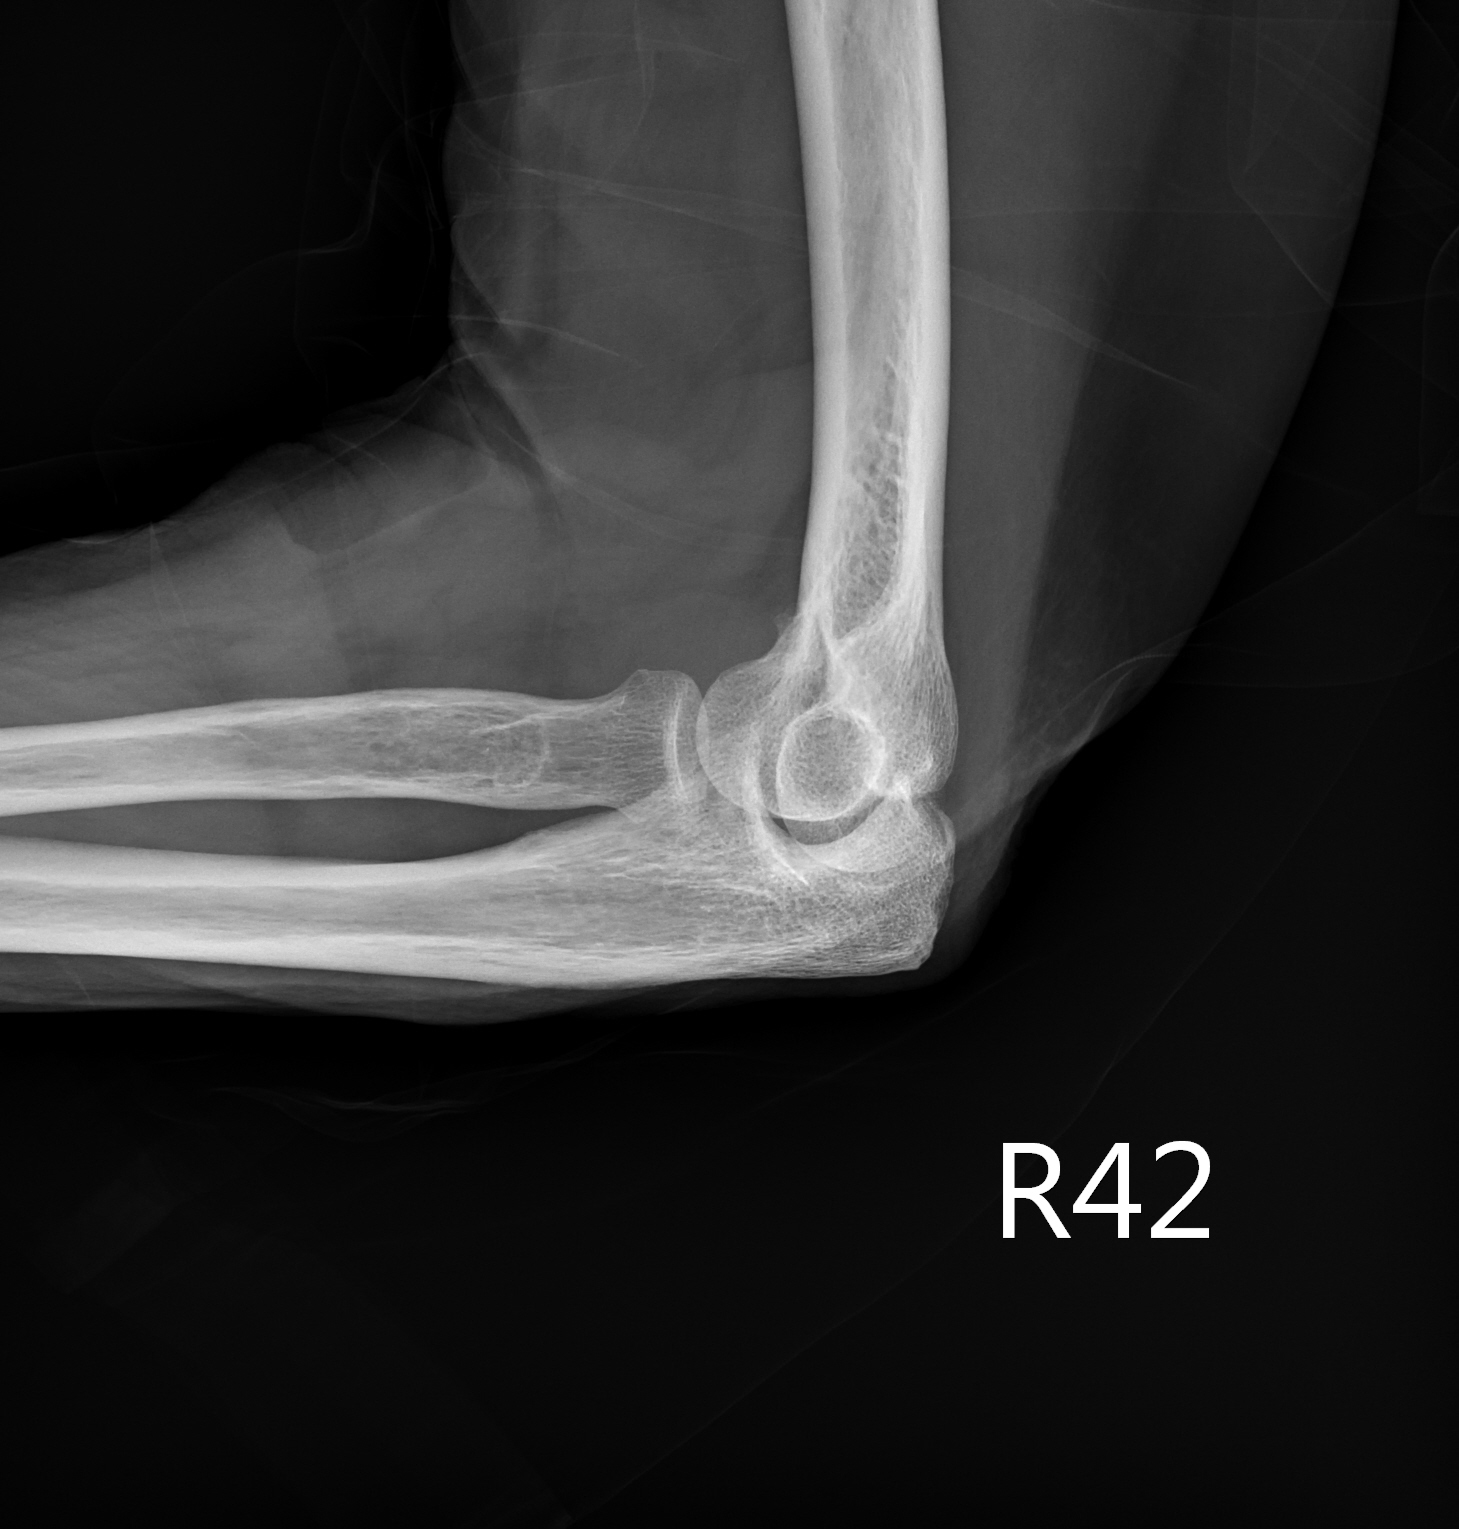

X ray image showed chondrocalcinosis over triangular fibrocartilage complex (TFCC) of right wirst (yellow arrow in Picture 2) and right knee (Picture 3). Asymmetrical joint space narrowing with spur formation (white arrow in Picture 4) of right knee was seen, compatible with OA change. No fracture or joint erosion seen over right elbow. (Picture 5).

Picutre 5 Right elbow